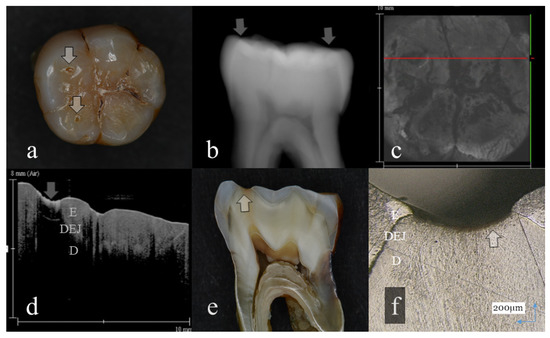

Figure 3.

Tooth wear with slight dentin exposure (score 3): (a): Occlusal view. The buccal cusps and distal surface were flattened (arrows); (b): Digital intraoral radiography. Remaining enamel at the occlusal distal surface was thinned (arrow); (c): OCT en face intensity projection; (d): SS-OCT image. Occlusal enamel was worn showing the flattened surface. Loss of enamel reached to the DEJ with the slight involvement of dentin (arrow): (e): Histological view. Occlusal enamel wear reached to the DEJ depth (arrow); (f): CLSM image of histological view. Slight dentin exposure at the cusp was observed (arrow). The corresponding dynamic slicing 3D video in is Supplementary Materials: Video S3. The upper right is a cross sectional image. The image on lower right is an en face image.

Three-dimensional OCT could detect the presence of dentin exposure within the tooth wear surface with pinpoint accuracy (Figure 3, Figure 4, Figure 5, Figure 6 and Figure 7, Videos S3–S7). Since dentin exposure may cause DH in response to mechanical and chemical stimuli during masticatory function, accurate diagnosis for dentin involvement appears beneficent for further maintenance and an intervention approach. Dentin contains 50 vol% of organic structure and scatters light, and signal attenuation of the OCT image through the dentin is higher than the enamel [29]. Optical dissimilarity between the two structures facilitates the discrimination of the tooth wear with and without dentin involvement. In this study, 3D OCT could clearly image the dentin exposure within the tooth wear surface, resulting in high diagnostic capacity and accuracy (Table 1, Table 2 and Table 3). OCT could also facilitate the characterization of exposed dentin surface changes, including the formation and thickness of transparent dentin [29].